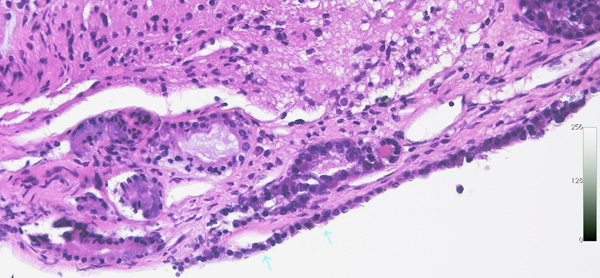

前頭側頭開頭 pterional approachで全摘出しました。発生母地は下垂体柄前面でしたが完全摘出しました。術後に下垂体機能は正常に保たれています。病理所見は一層の上皮細胞でのう胞壁が構成されることが特徴です。これをラトケのう胞と呼ぶかどうか議論のあるところで,おそらく正確には内胚葉のう胞 endodermal cystと診断します。